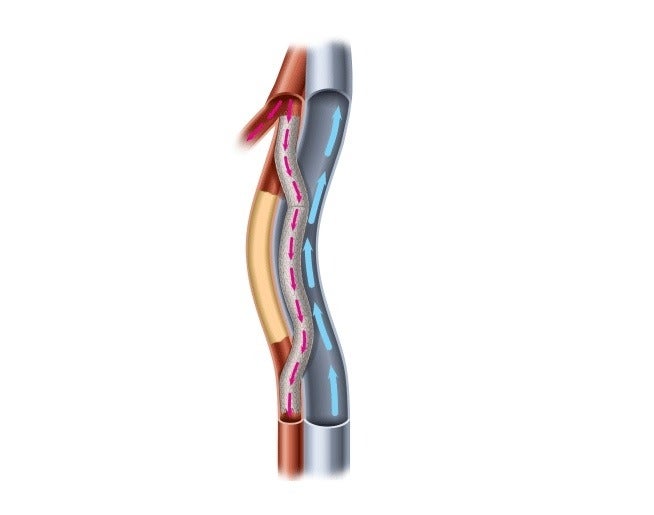

PQ Bypass gets FDA breakthrough device status for Detour System

PQ Bypass Announces CE Mark for DETOUR Percutaneous Bypass Technologies

PQ Bypass study meets safety efficacy endpoints MassDevice

PQ Bypass Incorporated docx 1 PQ Bypass Incorporated Performance

PQ Bypass Receives FDA Breakthrough Device Designation for the World

PQ Bypass Receives FDA Breakthrough Device Designation for the World

PQ Bypass Announces 60 Million Financing to Advance New Therapeutic

PQ Bypass Earns Frost amp Sullivan s European Technology Innovation Award

PQ Bypass Announces New President And CEO Medical Product Outsourcing

PQ Bypass Announces 60 Million Financing to Advance New Therapeutic